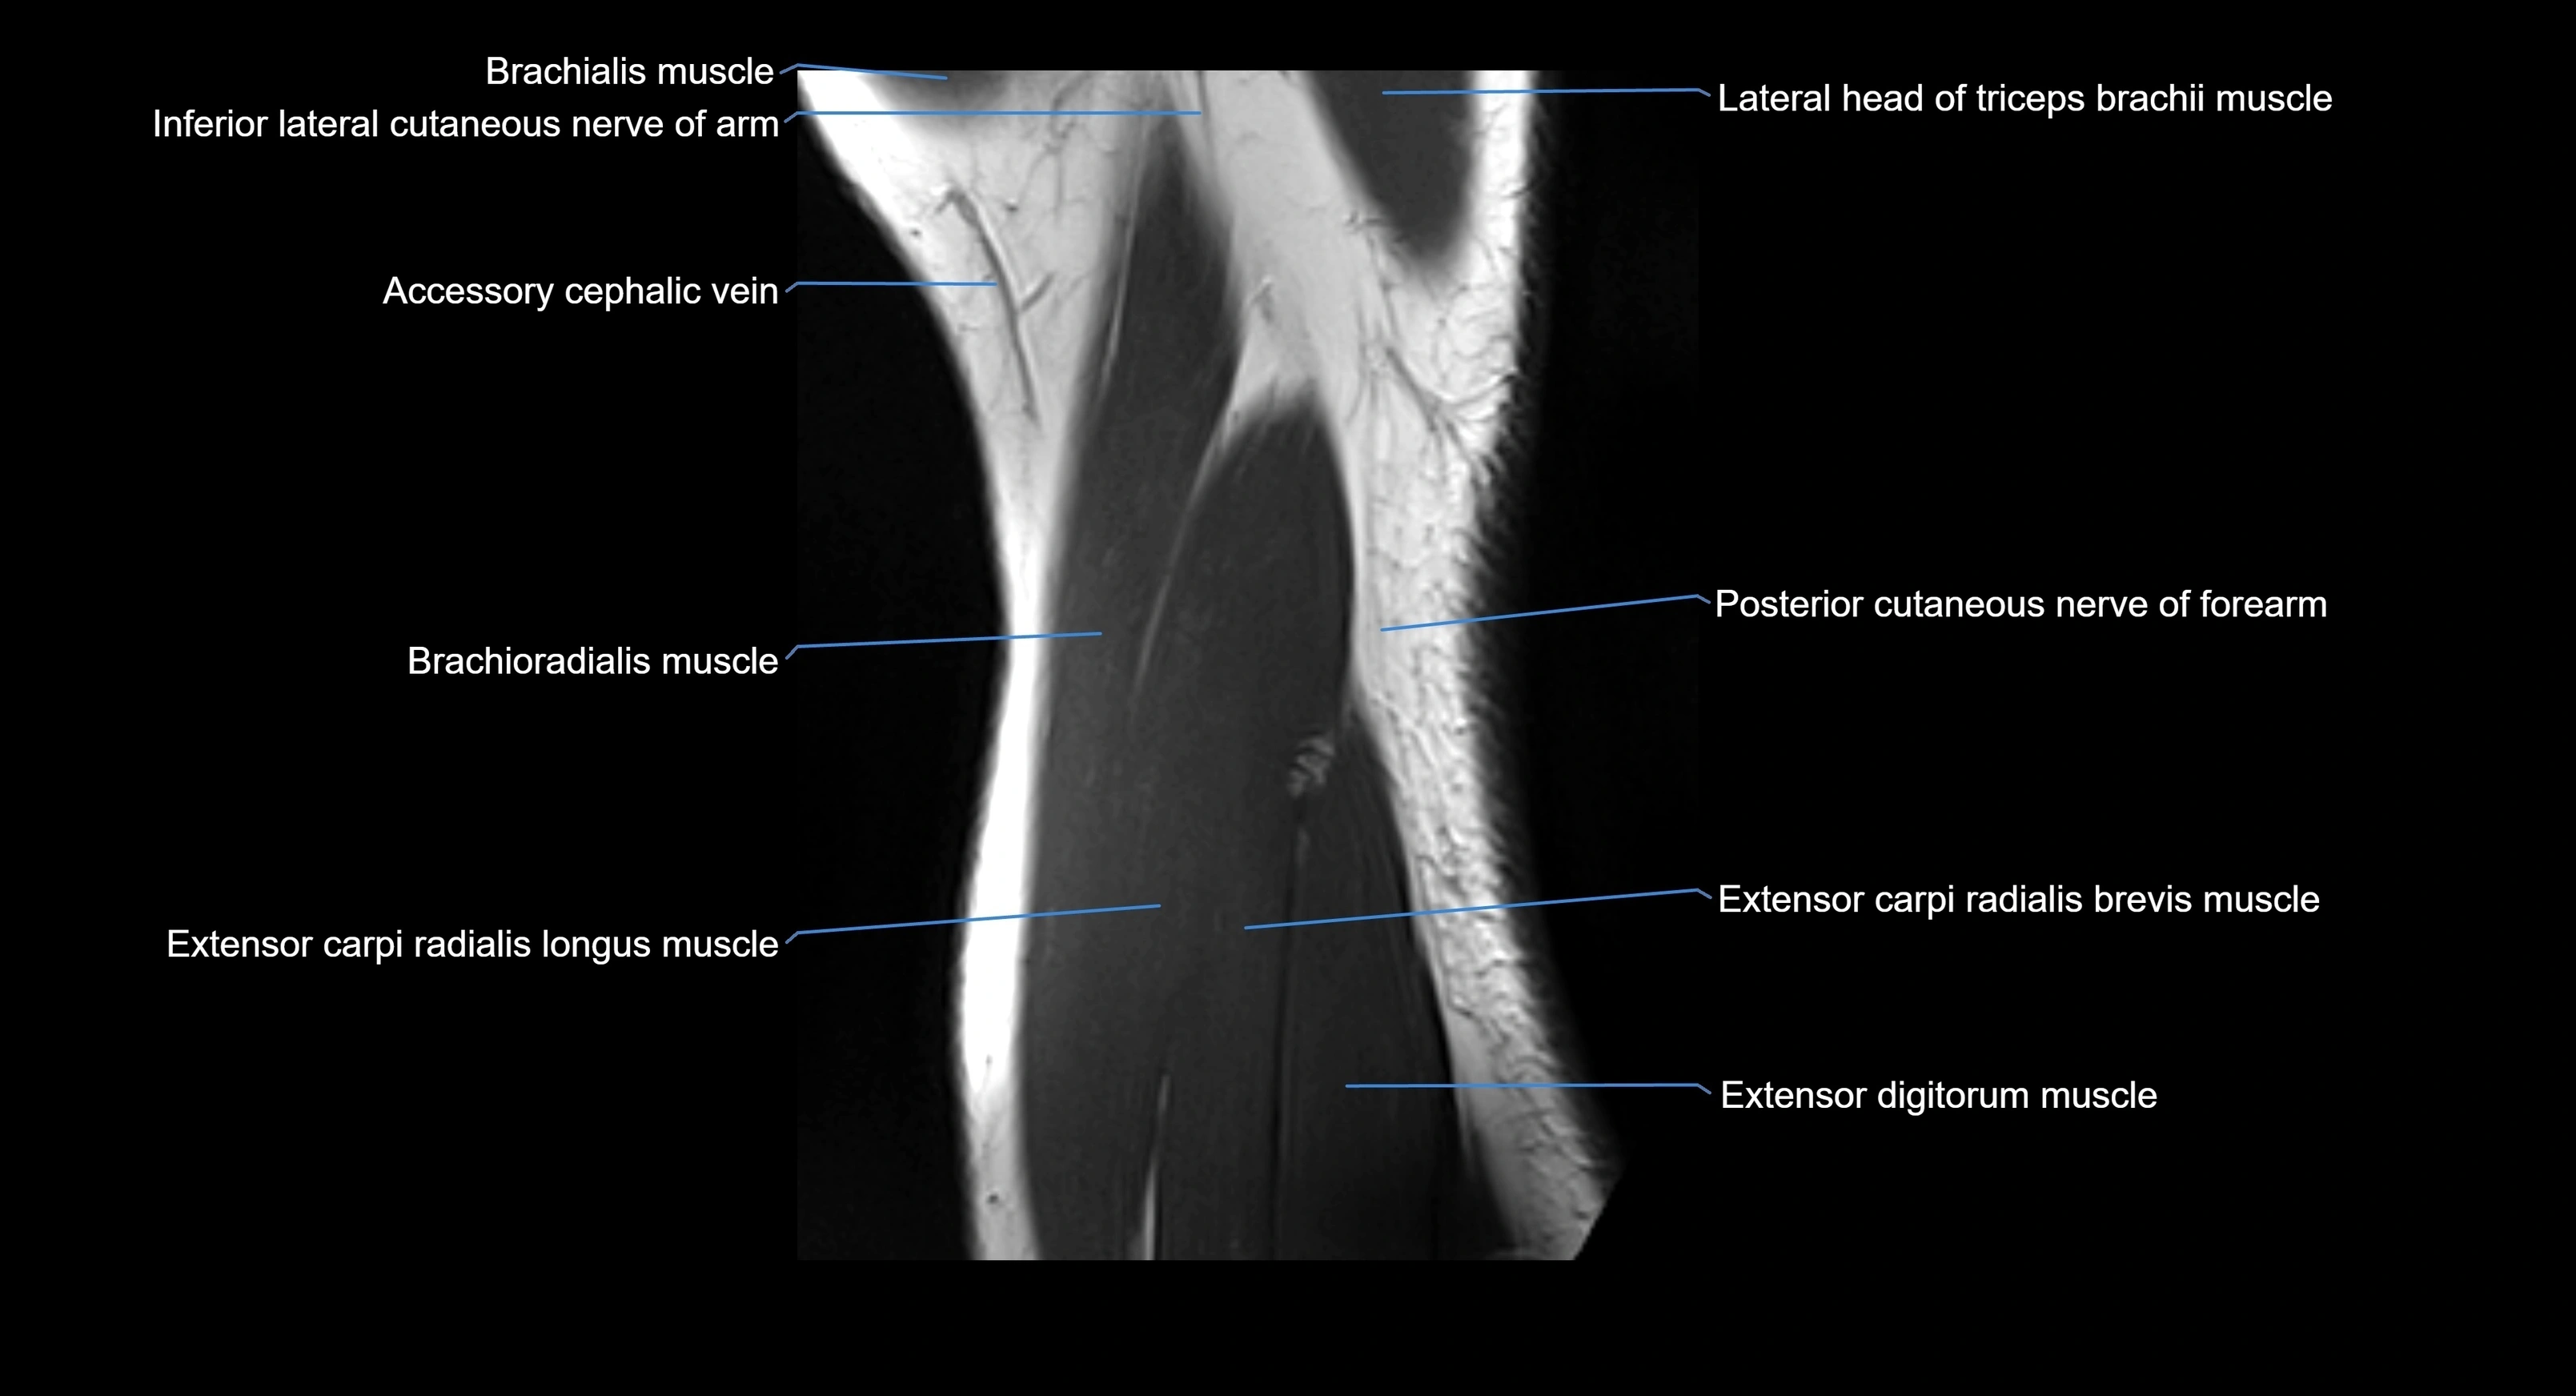

MRI image

image